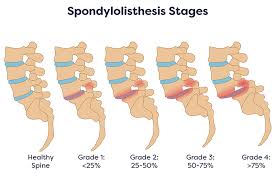

Spondylolisthesis is a condition wherein one vertebra slips forward on top of the lower vertebra. In such cases, endoscopic fusion/decompressio is done to relieve symptoms.